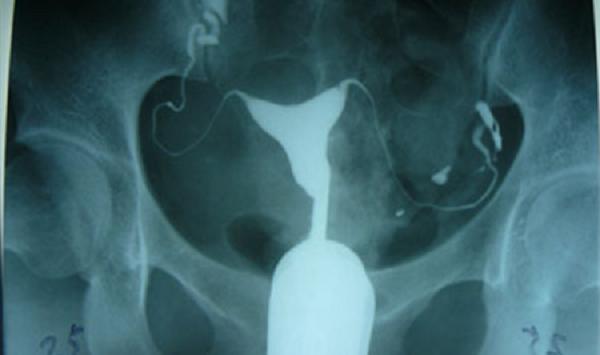

为什么都说输卵管造影不能轻易做?有什么危害吗?

今年28岁,备孕半年了,没做过安全措施,但一直没有动静,准备去做个不孕不育检查,前几个都没问题,就剩个输卵管造影没有做了,但是听说这个检查不能轻易做,想问一下,有..